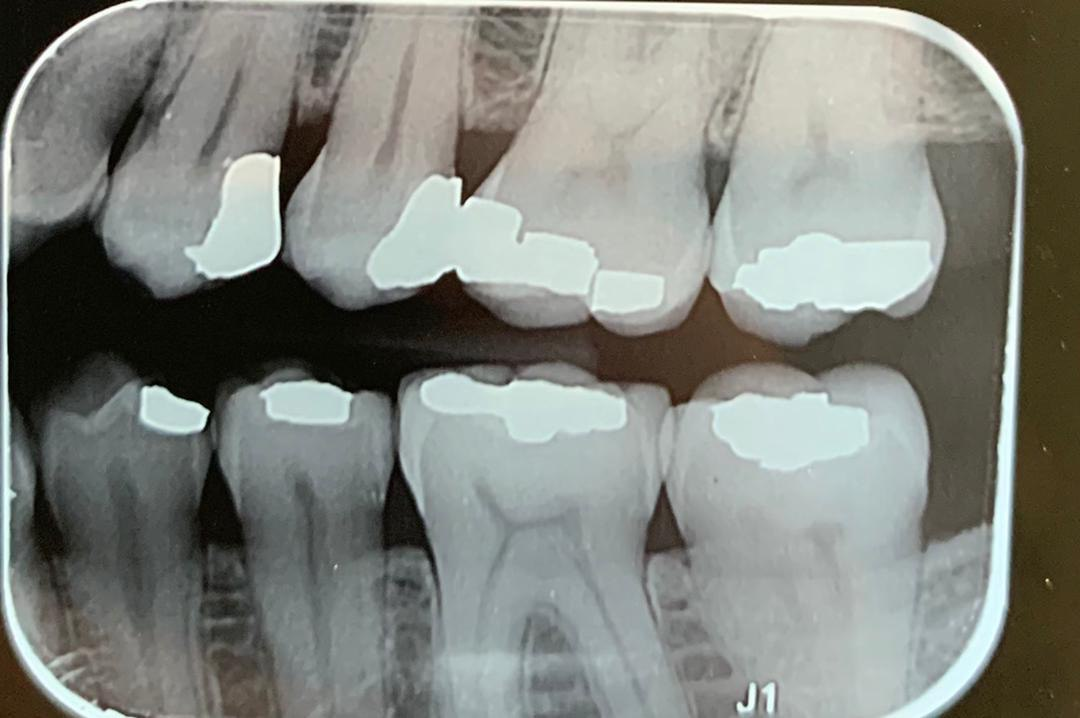

8. Which surface needs restoration?